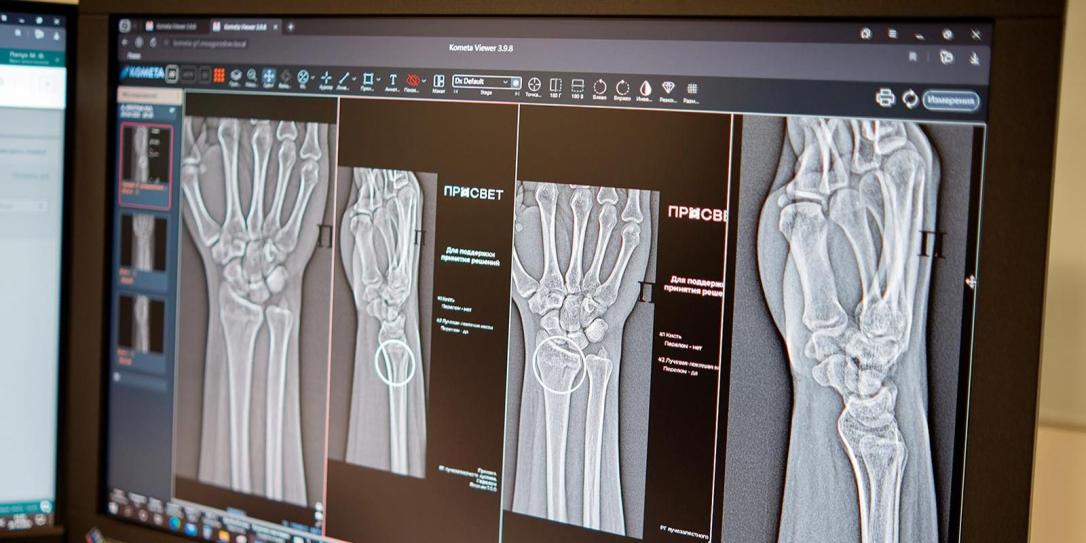

В столице внедрены две новые интеллектуальные системы для выявления сложных повреждений костных структур голеностопа и запястья. Эти технологии призваны предотвратить возможные осложнения: неправильное срастание костных тканей, возникновение деформаций и ограничение двигательных функций. Об этом рассказывает  mskpressa со ссылкой на портал mos.ru.

Она отметила, что цифровые помощники успешно работают со столичными рентгенологами более пяти лет, существенно упрощая анализ диагностических изображений.Кроме того, специалисты ввели в эксплуатацию две новые системы, ориентированные на выявление повреждений голеностопных и лучезапястных суставов — наиболее уязвимых и функционально значимых структур. Автоматизированные алгоритмы не только маркируют травмированные зоны, но и производят необходимые замеры, даже при множественных повреждениях на одном снимке.

Клиническая картина при переломах характеризуется отечностью и болевым синдромом, усиливающимся при двигательной активности. Своевременная и точная диагностика играет решающую роль в сохранении функциональности суставов. Интеллектуальные системы осуществляют многопараметрический анализ рентгенограмм, выполняют расчетные операции и сокращают время описания исследований. Алгоритмы способны идентифицировать даже минимальные повреждения и указывать на множественный характер переломов.